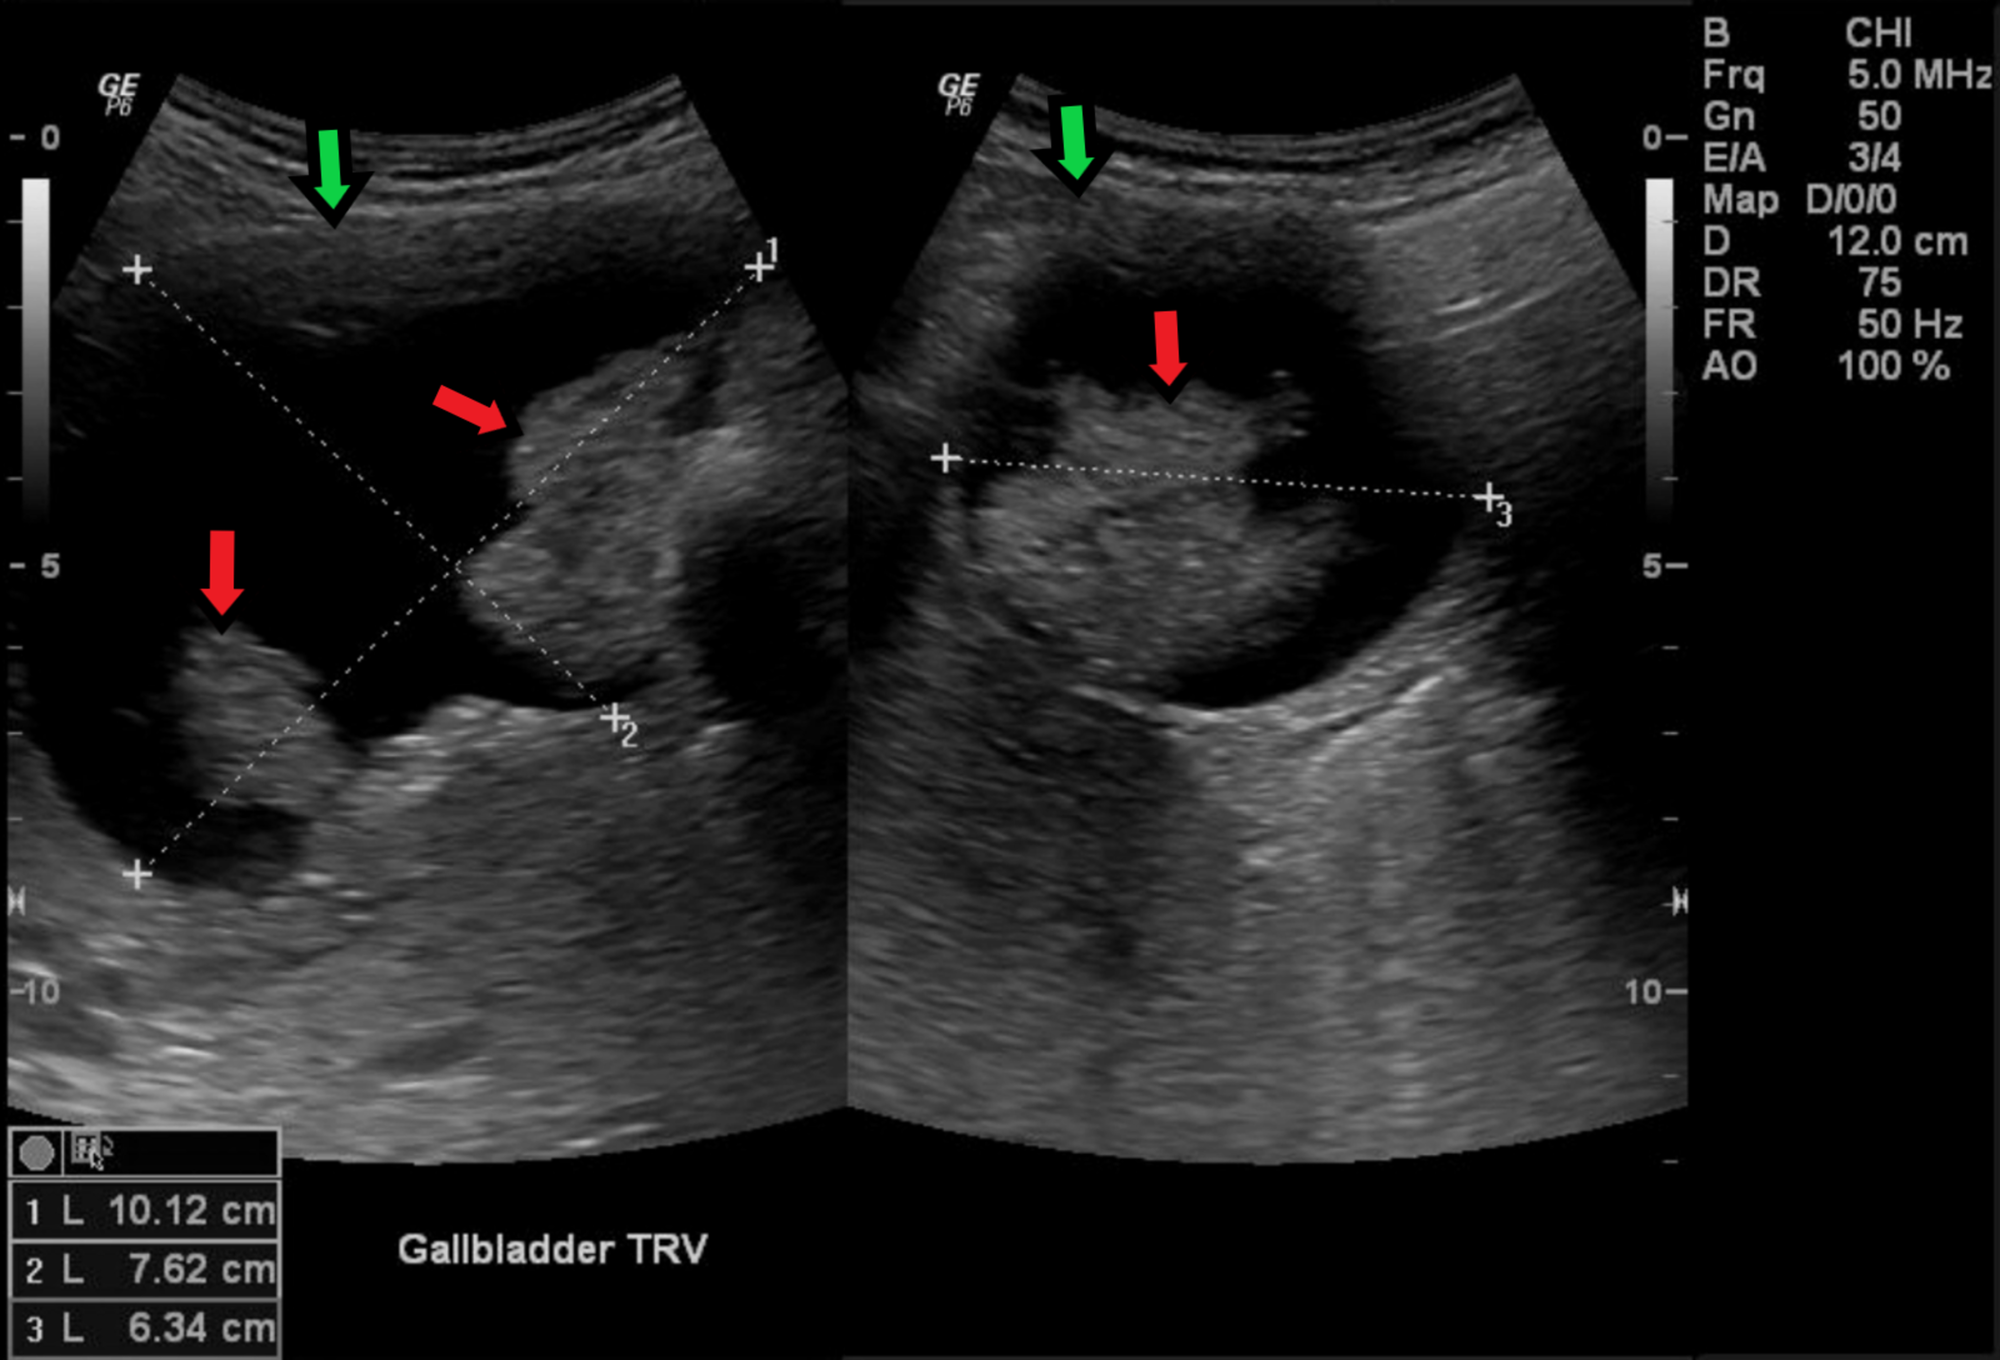

The cancer of gallbladder is rare. It accounts for less than 1% of the newly diagnosed cancers. The median age of presentation is 7th and 8th decade. The most common gallbladder cancer is adenocarcinoma. Squamous cell carcinoma is rare. The prognosis of gallbladder cancer is grim. Patient may survive for less than 6 months after the diagnosis. Reference: Bailey and Love's Short Practice of Surgery Image: https://www.cureus.com/articles/18437-evaluation-of-mucin-producing-gallbladder-carcinoma-using-magnetic-resonance-cholangiopancreatography-a-case-report